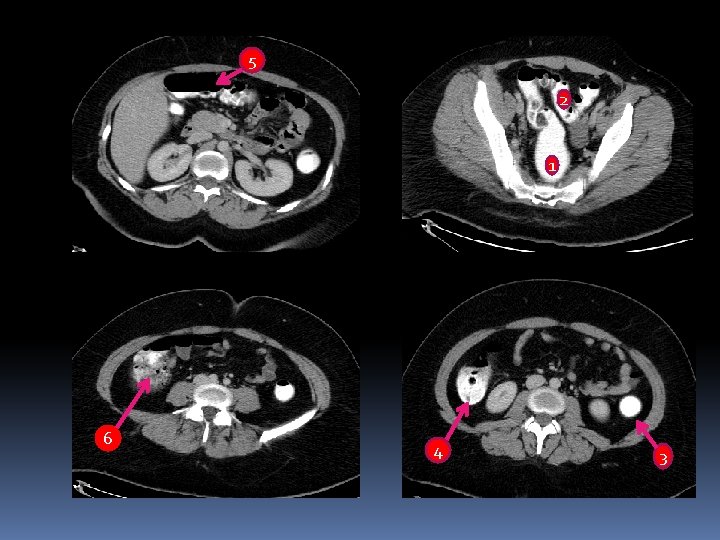

5 2 1 6 4 3

5 2 1 6 1 - Rectum 2 -Sigmoid colon 3 -Descending colon Transverse colon 6 -Cecum 4 3 4 -Ascending colon 5 -